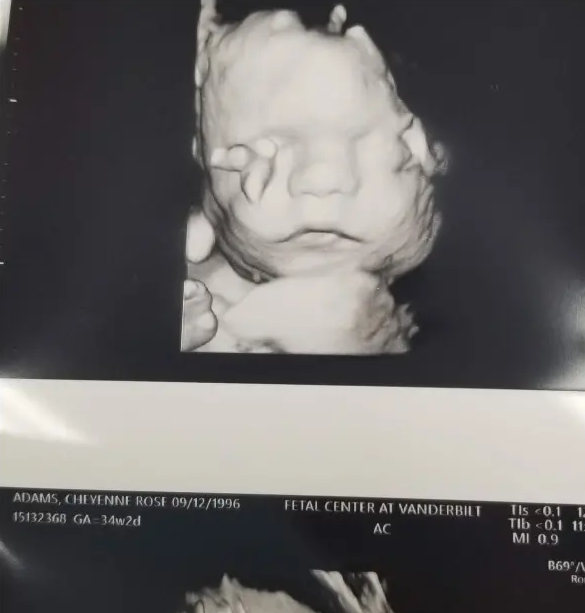

But as Cheyenne’s due date grew closer, they received some terrible news. Doctors told them that their unborn baby was ‘broken and breaking.’

Leo’s grandmother shared the full story with Love What Matters, saying the little boy was diagnosed with Osteogenesis Imperfecta, also known as ‘brittle bone disease.’

The condition makes the bones very weak and can easily break. Other symptoms include loose joints, respiratory problems, and hearing loss.